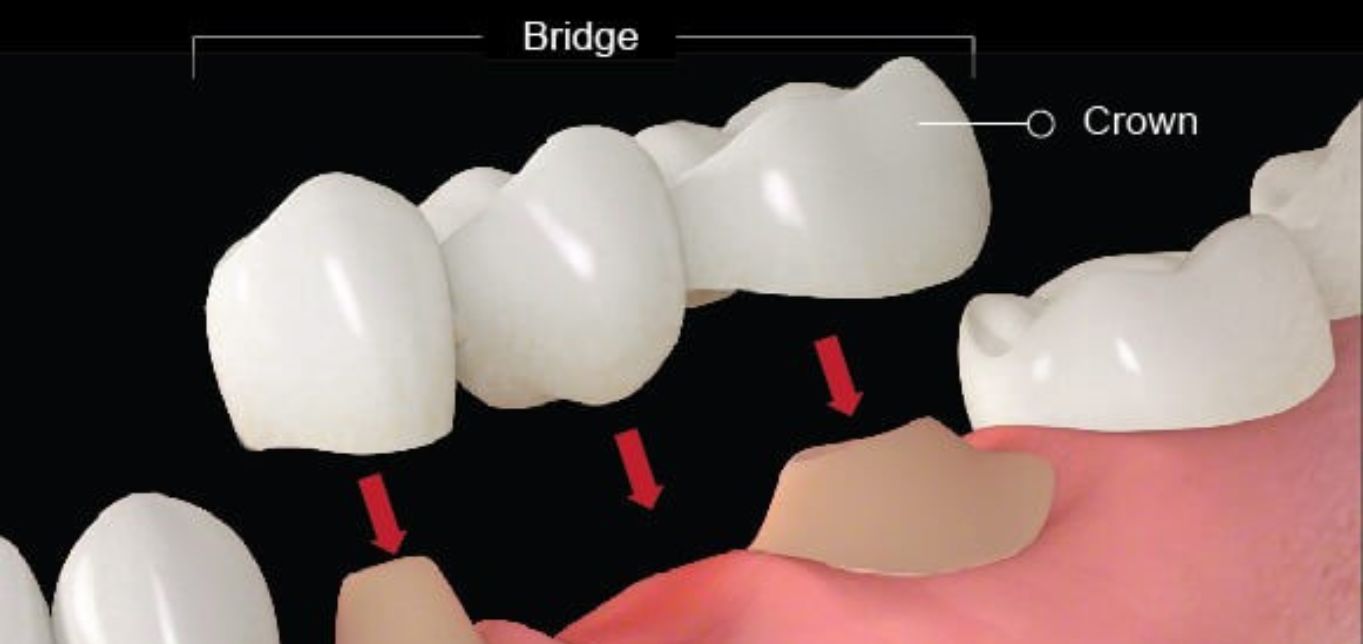

- Crowns and Bridges